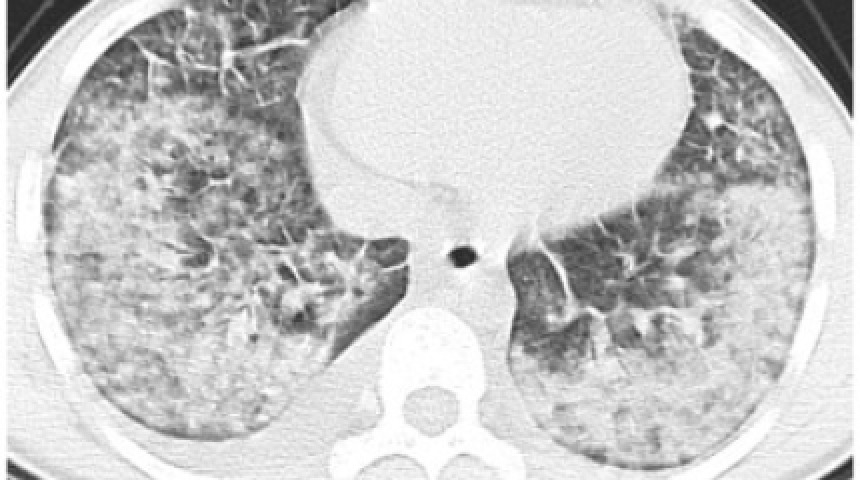

加熱菸產生嚴重肺部疾病,需葉克膜急救

台灣拒菸聯盟

2020/11/29 12:49

4,807

1

104